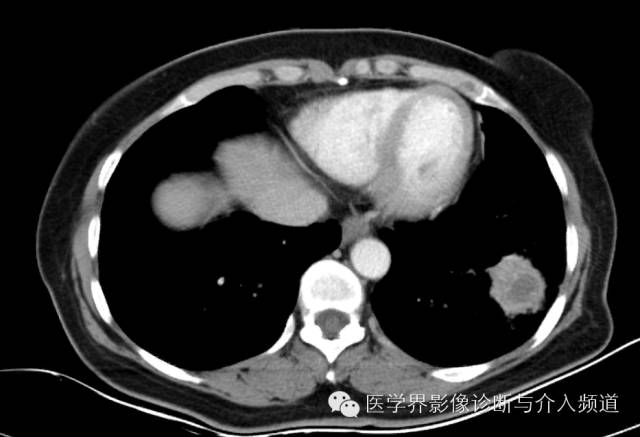

左下肺硬化性血管瘤1例CT影像表现

左肺下叶可见软组织密度肿块影,形态不规则,边界不光整,与胸膜粘连不清,周围肺组织呈磨玻璃密度改变,病变内部不均匀强化,低密度区不强化。

硬化性血管瘤

病变形态:圆形、椭圆形,单发,边缘光整,境界清晰,毛刺征、空洞、胸膜凹陷征罕见,少数可见浅分叶。

其他征象:钙化、囊变(与出血有关)、周围晕征(非特征性)、周围肺组织肺气肿、增强扫描明显均匀强化(与病变内血管瘤区、乳头区、硬化区、实变区有关)、贴边血管征(肿瘤推挤周围血管,较具特征性)、纵膈及肺门淋巴结(罕见,但有报道)。